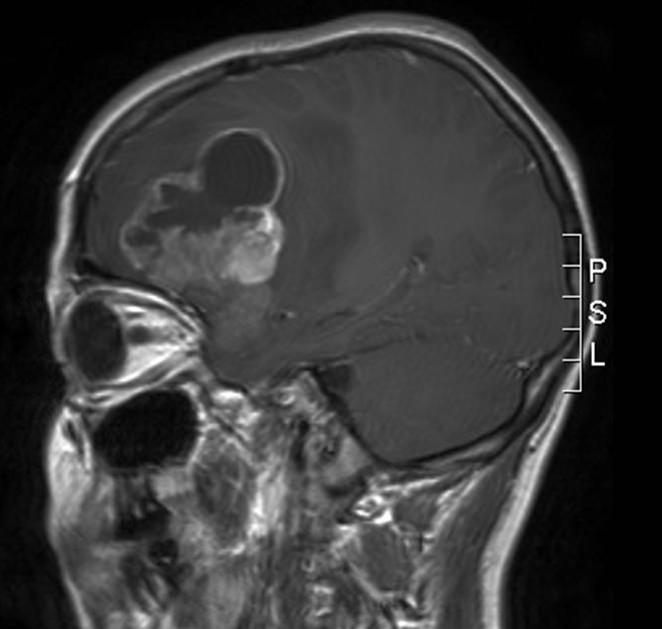

Billedet viser et anaplastisk ependymom, som er en malign hjernesvulst.